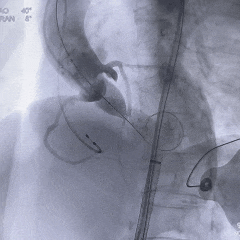

瓣膜0位初始定位

瓣膜稳定释放至全展开

工作位造影:无冠窦侧瓣下2mm左右,瓣膜形态直筒

左冠切线位,可见左冠开口无遮挡

多角度观察,确认瓣膜稳定